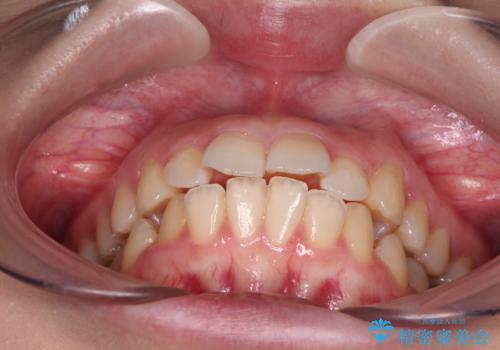

- 上下の前歯が突出しており、口が閉じにくいとのことで来院された患者様です。

上下前歯が著しく前突している状態であったので、上下左右の第1小臼歯4本を抜歯し、ワイヤー装置にて矯正治療を行うこととしました。

舌の突出癖があり、前歯の移動量も多くなるため、治療期間は長くなると予想されましたが、13ヶ月という予定の半分程度の期間で終えることができました。